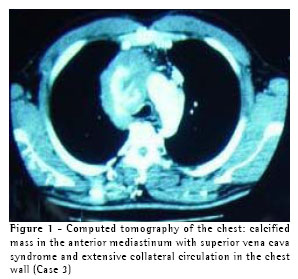

A 35-year-old previously healthy male presented with headache accompanied by cervical and facial edema for seven years, the symptoms having been incapacitating for the last two years. The working diagnosis was superior vena cava syndrome, and the patient was submitted to computed tomography of the chest, which revealed a mass in the anterior mediastinum, with a calcified center, invading the superior vena cava (Figure 1). In December of 2001, the patient was submitted to video-assisted thoracoscopy and a biopsy of the mass was carried out. The results of the frozen biopsy examination were inconclusive. A definitive, reviewed anatomopathological examination revealed dense adipose connective tissue infiltrated by atypical cells. Based on the immunohistochemical test results, the differential diagnosis between infiltrative neoplasia and entrapped reactive mesothelium was inconclusive. One year later, radiotherapy was unsuccessful, and there was an enlargement of the lesion as well as formation of significant collateral circulation revealed by a computed tomography scan of the chest. The patient was subsequently submitted to median sternotomy, during which significant sclerosis and fibrosis of the mediastinum were found. Subsequently, the left brachiocephalic vein was grafted to the right atrium using an 8-mm PTFE stent (Figure 2). In the postoperative period, the patient presented signs and symptoms of congestive heart failure, which were controlled using classic measures. The patient was discharged while still being treated with warfarin and has been in outpatient follow-up treatment for two months, his symptoms being well compensated. Anatomopathological examination revealed sclerosing mediastinitis. (Figure 3)

On computed tomography scans, the most common pattern is that of a localized mass, with attenuation of the soft parts, accompanied by irregular calcifications. The other pattern consists of tissue with diffuse homogeneous attenuation of the soft parts throughout the mediastinum, and this tissue is usually calcified. Either of these patterns can be accompanied by compression or entrapment of the tracheobronchial tree, of the major mediastinal vessels or of the esophagus. Greater pulmonary attenuation, thickening of the interlobular septa and peribronchial distention are seen when there is obstruction of the pulmonary veins.